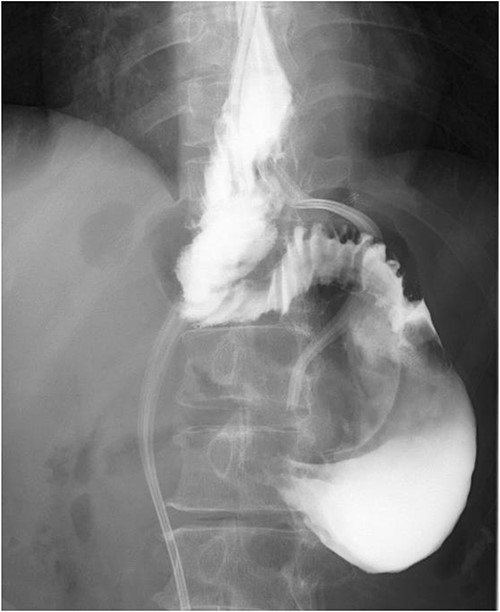

A 60-year-old female with dysphagia and vomiting visited the university hospital. In 2007, she underwent esophageal diverticulum resection (procedure unknown) with a diagnosis of an esophageal diverticulum, which subsequently recurred. In 2011, she underwent a transesophageal hiatus diverticulectomy and a fundoplication (Nissen procedure) at a local hospital. In 2013, dysphagia and vomiting appeared. The patient was diagnosed with recurrence and underwent balloon dilatation for follow-up. In 2015, the patient came to our hospital due to persistent symptoms. After one balloon dilation, the patient did not show any improvement and was referred for surgery. Esophageal fluoroscopy revealed a diverticulum 5 cm in size in the lower esophagus just above the eruption. There was no significant change in the diverticulum size before and after dilation (Figs 1 and 2). Gastrointestinal endoscopy revealed a diverticulum in the lower esophagus, with a residue accumulation (Fig. 3). The esophagus directly below the diverticulum was narrowed. The patient was diagnosed with recurrent lower esophageal diverticulum and underwent surgery.

Esophageal fluoroscopy (before dilation). There was a 5 cm-sized diverticulum in the lower esophagus just above the eruption.

Preoperative esophageal fluoroscopy (after dilation). There was no significant change compared to the pre-expansion period.